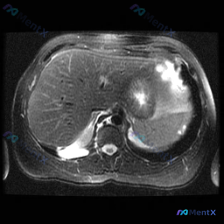

这是一张腹部MRI轴位T2加权图像,可见一个边界清晰、形态规则的类圆形极高信号病灶,信号强度接近脑脊液(典型的“灯泡征”样表现),内部信号均匀,无明显分隔、结节或壁增厚,也未见对周围组织造成明显压迫或占位效应。

原始分析将病灶定位于肝脏右后叶,考虑为「单纯性肝囊肿」——这看起来非常符合肝囊肿的典型影像。

但关键的临床问题是:临床明确指向的是“脾脏病变”。

这里必须停下来仔细核对:脾脏位于左上腹,肝脏位于右上腹。如果强行将一个脾脏区域的病灶解释为肝囊肿,这属于严重的解剖学谬误,可能导致完全错误的临床决策。

- 脾血管瘤:这是脾脏最常见的良性肿瘤,T2像上可表现为典型的极高信号(灯泡征),边界光滑。增强扫描通常呈现「周边结节状强化,延迟期向心性填充」的特点。

整体来看,如果定位确实在脾脏,更倾向于脾血管瘤或单纯性囊肿这类良性病变,但必须通过增强扫描彻底排除高危情况。